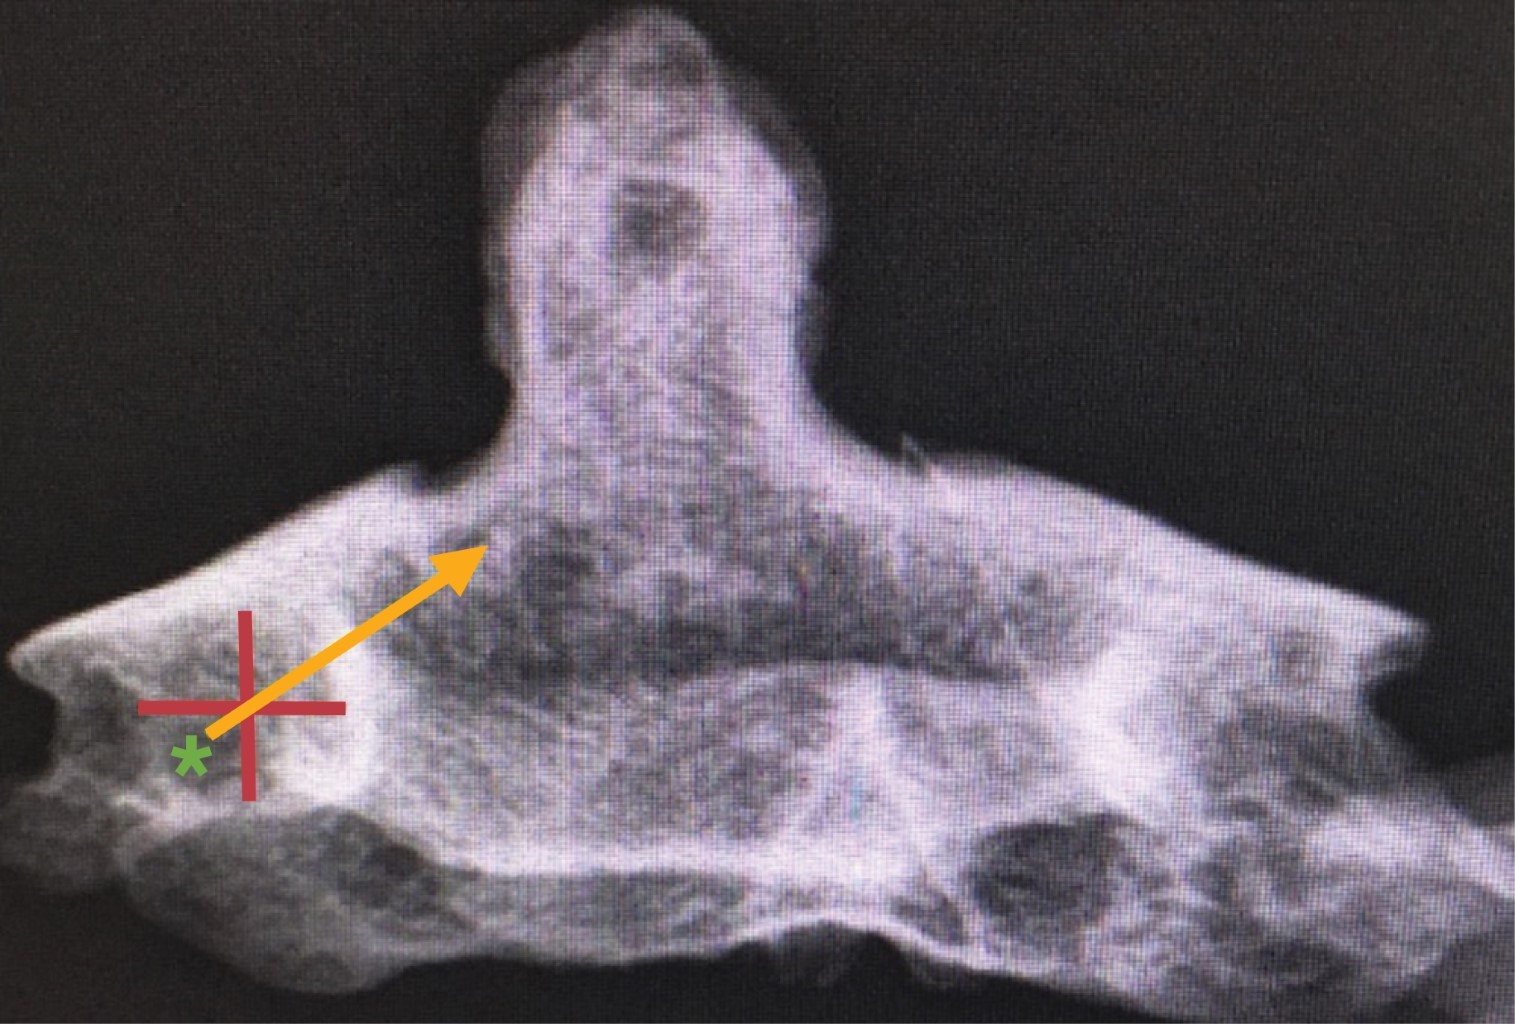

Un punto que consideramos importante es que el tornillo no debe pasar la porción medial de la carilla articular superior por riesgo de perforar la cortical anterior del cuerpo vertebral y lesionar estructuras anteriores (Figura 3). Recomendamos realizar el estudio tomográfico de control en el mismo día de la cirugía y evaluar la posición de su tornillo (Figura 4).

Figura 3